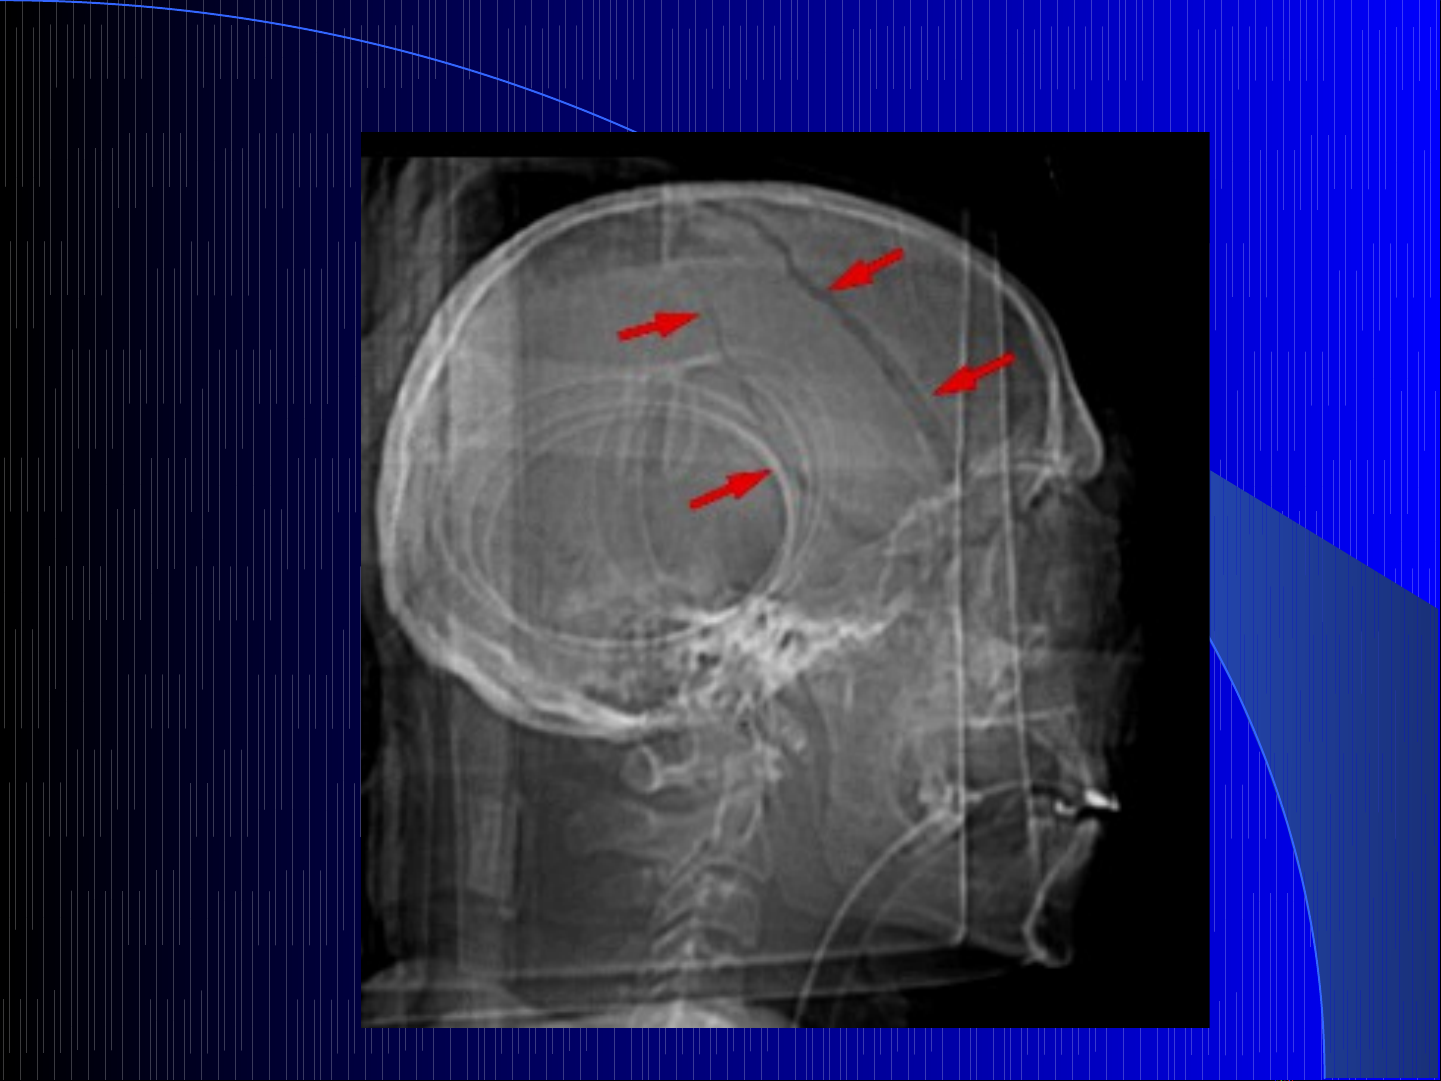

Máu t ngoài màng c ng ụ ứ

Máu t dụiướ màng c ng c p tính ứ ấ đơn thu n ầ

Ch p s th ng nghiêng không có tác d ng ụ ọ ẳ ụ

CT không tiêm, n u m t ý th c, dùng kháng VTM ế ấ ứ

Ch p l i CT sau 24 gi , n u :ụ ạ ờ ế

–CT ban đuầ th c hi n trự ệ cướ 3 gi sau ch n thờ ấ ương

–Không c i thi n ho c lâm sàng n ng lên ả ệ ặ ặ

–Tăng áp l c n i s ự ộ ọ